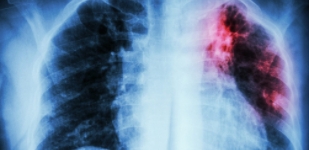

- пневмонию,

Наличие квалифицированных специалистов и индивидуальный подход к каждому посетителю позволяют достичь значительного улучшения самочувствия и повышения иммунитета всех наших пациентов при лечении органов дыхания. Важность своевременной диагностики и адекватного лечения обусловлена высокой вероятностью развития осложнений даже при небольших проблемах – от хронического бронхита до обструктивного легочного заболевания или пневмосклероза.